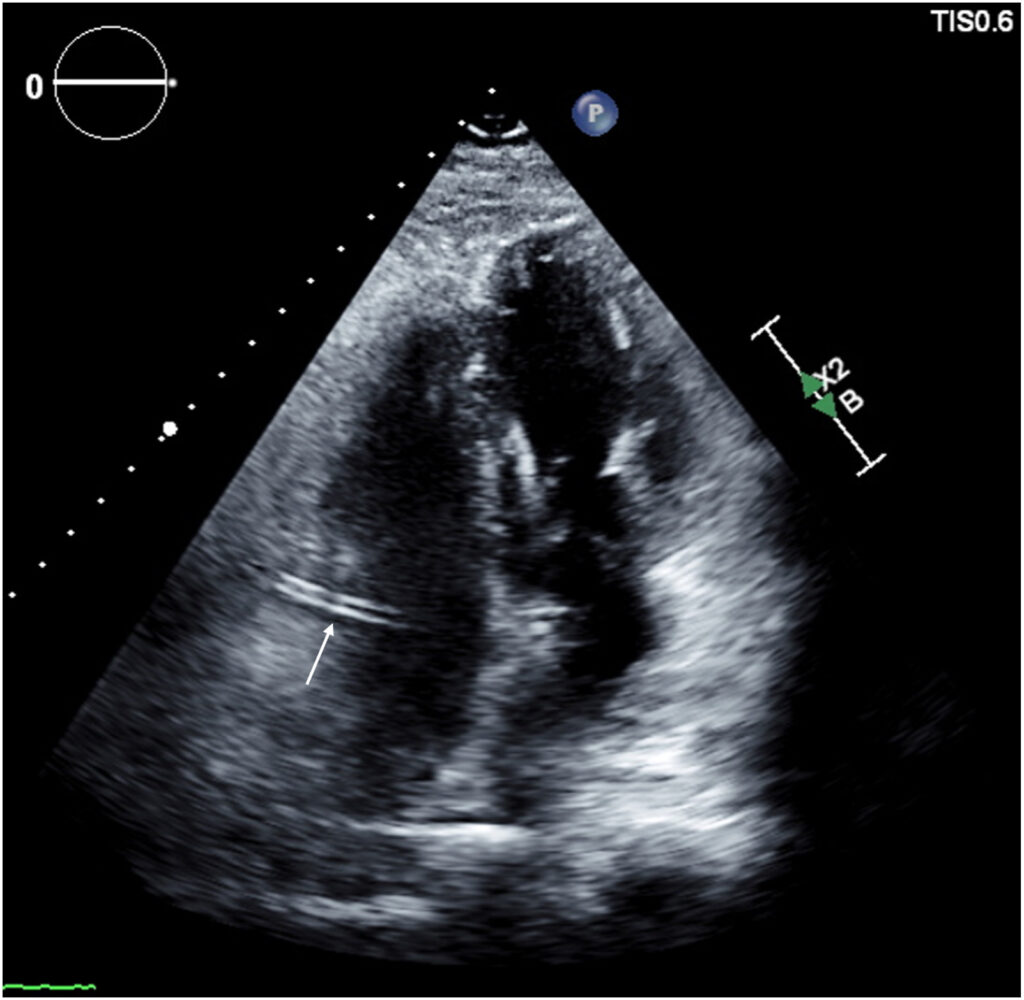

Foi observado, porém, na janela apical 4C, um padrão distinto de duas linhas ecogênicas em paralelo com curso intra-atrial, não correspondendo a nenhuma estrutura anatômica habitual desta cavidade.

O achado, inicialmente descrito como “sinal do trilho do trem” (train track sign) pela equipe assistente, levantou suspeitas de trajeto anômalo coronário motivando, portanto, a solicitação de AngioTC de artérias coronárias.

Neste caso específico, o achado não habitual de duas linhas ecogênicas em paralelo (à semelhança do aspecto anatômico do RAC Sign) localizadas no interior do AD levantou a suspeita diagnóstica, um padrão denominado pelos autores de “train track sign”.